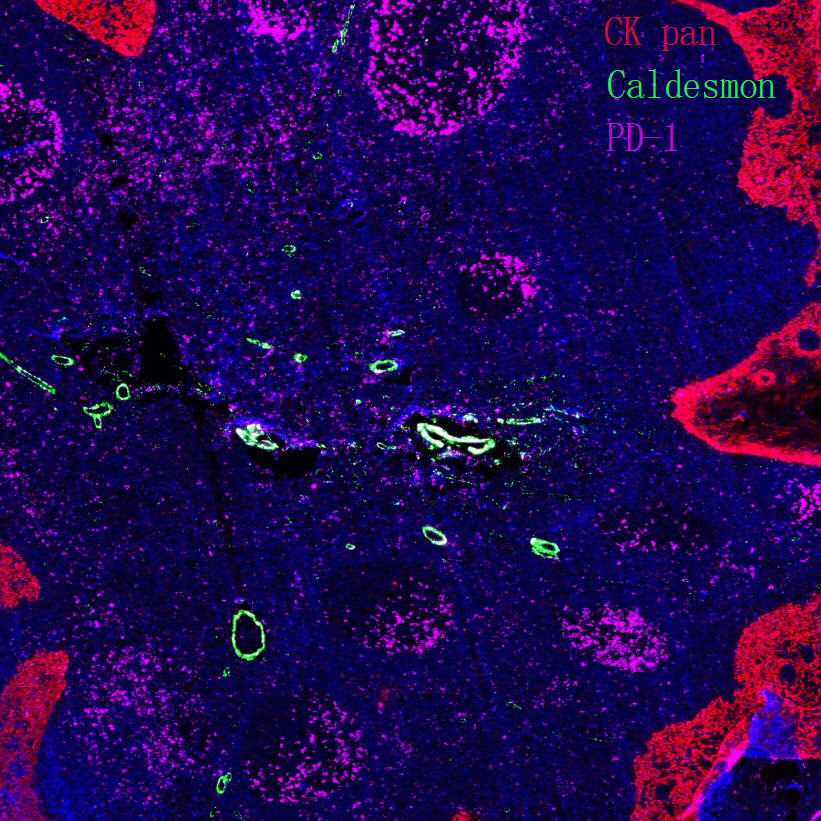

II. Problem Analysis in Staining Operation

The staining process includes dewaxing, antigen retrieval, blocking, washing, primary antibody incubation, secondary antibody incubation, DAB chromogenic development, hematoxylin counterstaining, etc. The detailed control of each step directly determines the staining quality.

(VIII) Issues Related to Tissue-Specific Differences

Common problem: Staining results are inconsistent with expectations, showing negative or weak positive detection.

HER-2 staining results vary among different breast cancer samples.

Recommendation for Resolution: Set up positive tissue section controls. Due to significant differences in the expression of the same protein among different tissues, controls can help exclude the influence of the tissues themselves.